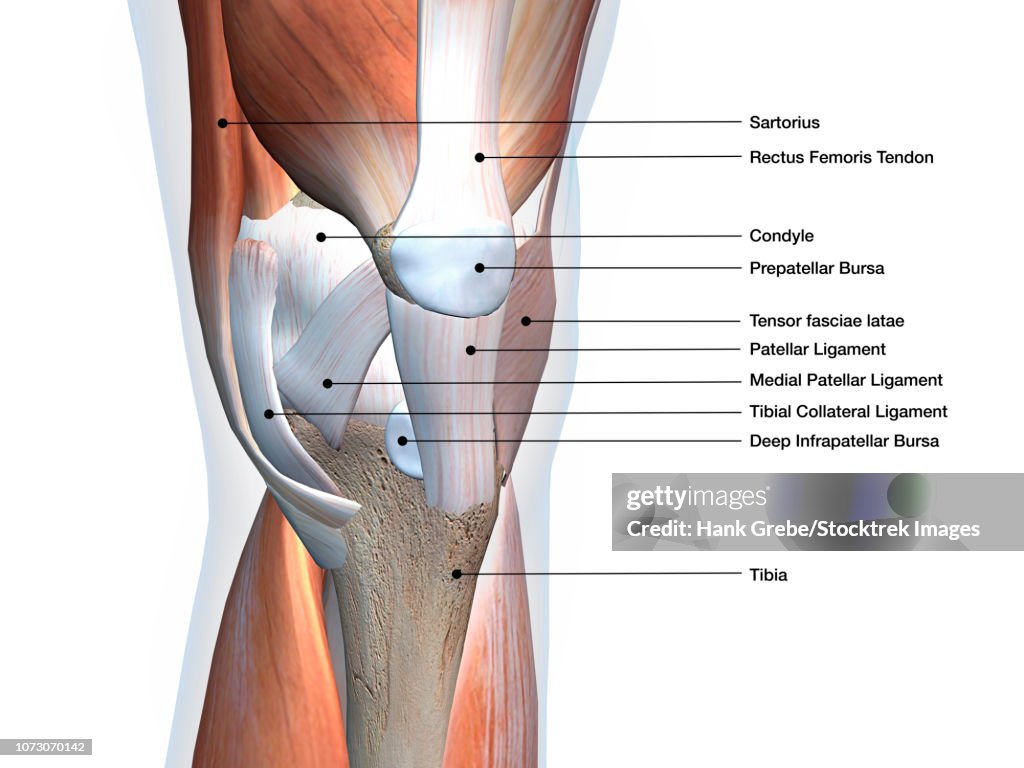

Knee joint showing muscles and ligaments with labels. - Stockillustratie

Knee joint showing muscles and ligaments, labeled on white background.

Getty ImagesKnee Joint Showing Muscles And Ligaments With Labels, Stockfoto Download premium, authentieke Knee joint showing muscles and ligaments with labels. stockillustraties van Getty Images. Verken vergelijkbare stockillustraties met hoge resolutie in onze uitgebreide visuele catalogus.Product #:1073070142